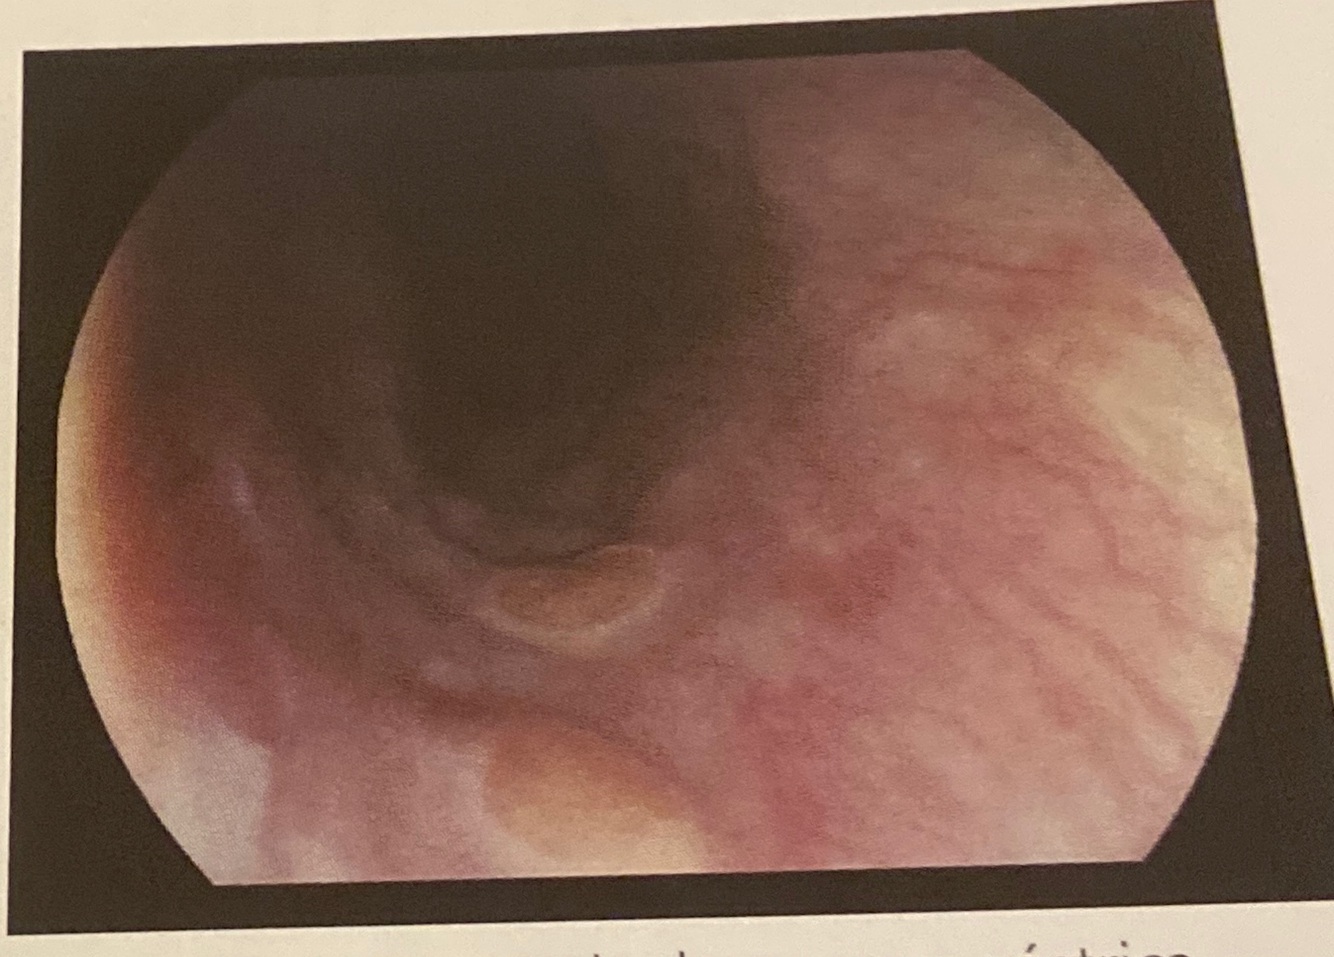

Flebectasia. Dilatação venosa focal,

de coloração característica.